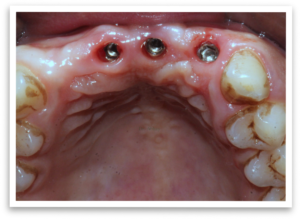

Despite the obstacle, our team at City Dental Clinic didn’t give up. We proposed a specialized procedure – ridge split followed by ridge expansion. This involved carefully splitting the existing bone ridge and gradually widening it. Simultaneously, a bone grafting technique (GBR) was employed to add additional bone volume. This innovative approach allowed for the immediate placement of implants, maximizing efficiency and minimizing treatment time.

Following the implant placement, a healing period of six months was crucial. Once healed, the prosthetic phase began. Through collaboration with our skilled lab technicians, we created a customized solution. A Paulo Malo bridge was chosen for the upper jaw, offering exceptional strength and aesthetics. The lower jaw received a screw-cement retained prosthesis, ensuring a secure and comfortable fit.